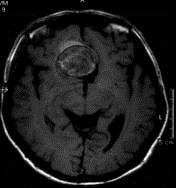

问题 病历摘要:??患者男性,56岁,因右侧视力下降伴视野缺损2个月来院就诊,诉头痛,无明显头晕,无视物重影,无恶心呕吐,无肢体抽搐,无肢体乏力,胃纳佳,大小便正常,既往史无特殊,入院检查:神志清楚,言语清楚,体毛分布正常,左侧视力4.6,右侧视力4.0,粗侧右颞侧视野缺损,左侧正常,颈软,四肢肌张力正常,肌力正常,病理征(-)。 该患者入院应行下列那些检查?

选项 A.头部CT B.头部MRI C.性激素检查 D.视觉诱发电位 E.视野检查 F.癌胚抗原检查

答案 ABCDE